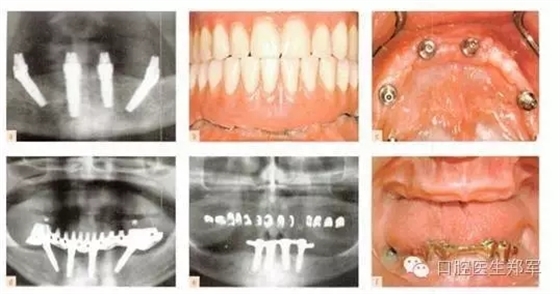

剩余牙槽骨的客觀解剖因素決定是否可以放置全牙弓種植體。在上頜骨,上頜竇提升通常是一個選擇,但是可能會導(dǎo)致極高的牙冠長度和不協(xié)調(diào)的冠根比。所謂“All on Four”,四個種植體支持式固定修復(fù)一直存在爭議,支持者和懷疑者都在等待長期的研究結(jié)果(圖3和4)。下頜后牙種植體的位置是由剩余牙槽嵴寬度和高度,以及不可預(yù)知的垂直方向上骨增量共同限制。5年的研究結(jié)果表明,種植體的存活和成功不受修復(fù)類型的影響。

圖3下頜的治療選擇。a到d 固定“All on Four”修復(fù)和遠中傾斜植入。(圖片由Dr. B Marshak提供)。e 和f 由四個種植體支撐的下頜覆蓋義齒。 |

圖4 種植支持的覆蓋義齒或4個傾斜種植體支持的固定種植體支持式的修復(fù)。“All on Four”已經(jīng)廣泛的傳播,懷疑者等待更可靠的證據(jù)結(jié)果。臨床圖像由Dr. B Marshak提供。 |